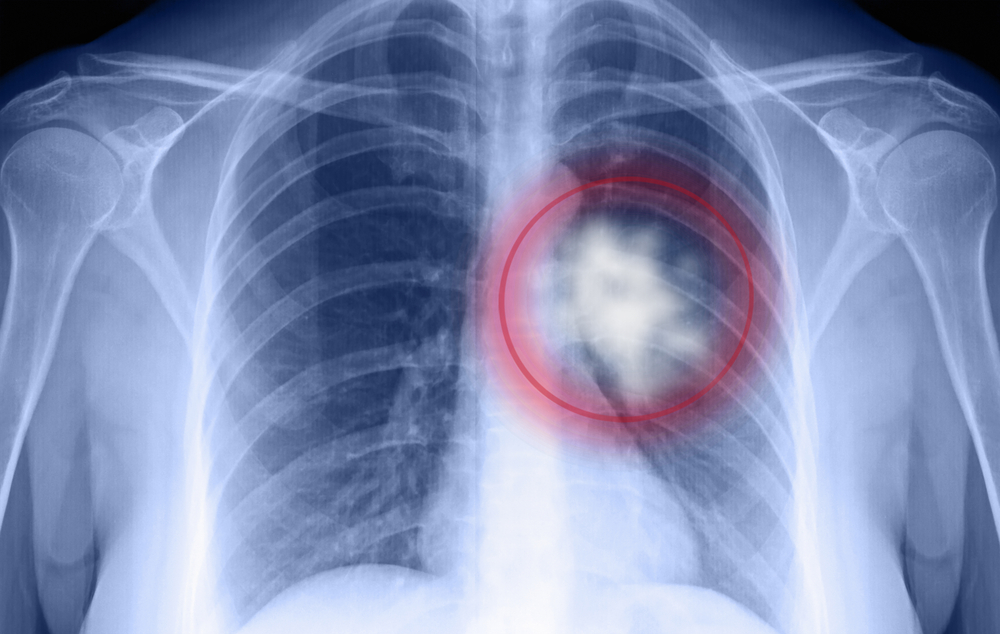

ជំងឺ​មហារីក​ទងសួត គឺ​ច្រើន​ប៉ះពាល់​លើ​បំពង់​ខ្យល់​ ឬ​ទង​សួត​ និង​ក្រពេញ​ទឹក​មាត់ ជា​ពិសេស​អាច​រាល​ដាល​ទៅ​សរីរាង្គ​ផ្សេង​ទៀត ​ប៉ុន្តែ​មហារីក​ប្រភេទ​នេះ​អាច​ព្យាបាល​បាន បើ​សិន​ធ្វើ​រោគវិនិច្ឆ័យ និ​ង​ព្យាបាល​បាន​ទាន់​ពេល​វេលា។ ភាគ​ច្រើន​ប្រុសៗ​គ្រប់​វ័យ​​ ងាយ​នឹង​កើត​មហារីក​ទងសួត ច្រើន​ជាង​ស្រីៗ។

ចំពោះ​ជំងឺ​នេះ បើ​​យើង​​បាន​​​ធ្វើ​រោគ​វិនិច្ឆ័យ​ឲ្យ​បាន​រហ័ស​ និង​ការ​ព្យាបាល​ឲ្យ​ទាន់​ពេល​វេលា​គឺ​អាច​បង្ការ​កុំ​ឲ្យ​រងផល​វិបាកដោយសារ​ជំងឺ​​ និង​បង្កជា​មហារីក​បាន។​ ​រោគ​សញ្ញា​​មហារីក​ប្រភេទ​នេះ​អាច​នៅ​ចំ​កណ្ដាល ឬ​នៅ​គែម​ៗបំពង់​ខ្យល់​ ខណៈ​រោគ​សញ្ញា​ចំ​កណ្ដាល​ អាច​ធ្វើ​ឲ្យ​ស្ទះ ​និង​​ហូរ​ឈាម​លាយ​ឡំ​ និង​មាន​អាការៈ៖